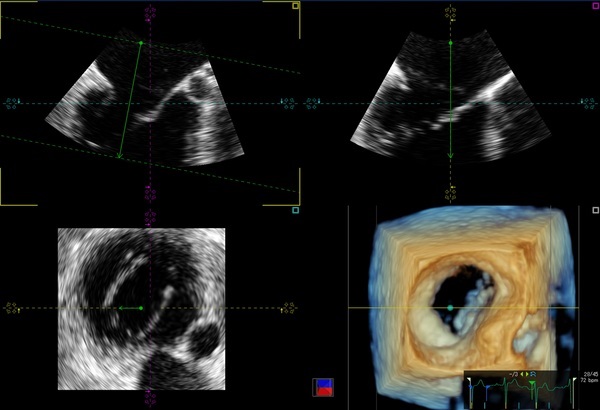

4D MV-ASSESSMENT

3次元画像表示を用いることにより僧帽弁の正確な形状の構築・定量評価を可能です。